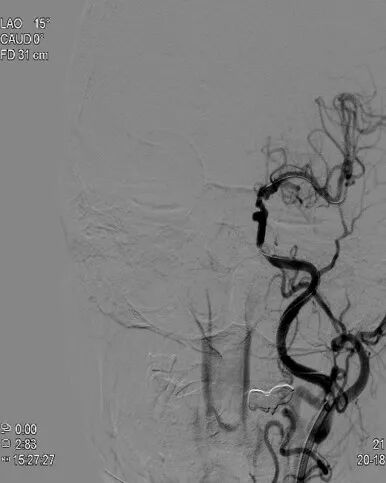

治疗中影像1

◆ 右侧颈内动脉以及右侧大脑中、前动脉显影良好,对左侧大脑中动脉部分代偿供血。

导丝怎么扩重磅!NOVA颅内药物球扩支架湖北首例植入!_https://www.jmylbn.com_新闻资讯_第6张

右侧颈内动脉造影

◆ 椎动脉、基底动脉脊大脑后动脉等各分支显影良好。

导丝怎么扩重磅!NOVA颅内药物球扩支架湖北首例植入!_https://www.jmylbn.com_新闻资讯_第7张

椎动脉造影

◆ 左侧颈内动脉C4段重度狭窄。

导丝怎么扩重磅!NOVA颅内药物球扩支架湖北首例植入!_https://www.jmylbn.com_新闻资讯_第8张

左侧颈内动脉造影